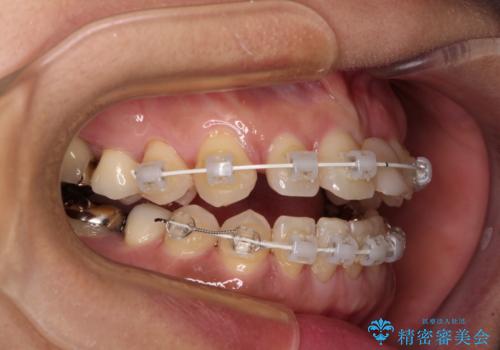

- 矯正装置

- 審美装置

当初はセラミック治療だけを希望されていましたが、上下前歯のデコボコが顕著であったため、セラミッククラウンにて治療する前に再度矯正治療を行った方が仕上がりがきれいになると説明し、再矯正を行うこととしました。

矯正治療により前歯横幅のバランスを整えた後に、上顎前歯をオールセラミックブリッジにて補綴治療を行うこととしました。

舌突出癖により、上下前歯が突出して離開してしまったため、舌のトレーニングを徹底的に行いました。